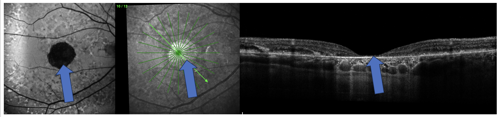

In addition, it is now widely accepted that GA may be difficult to identify on clinical examination alone. Ancillary testing such as OCT and fundus autofluorescence increase its visibility and make for an easier diagnosis (Figure 1).1

More recently, the Classification of Atrophy Meeting coined optical coherence tomography (OCT) based terminology—including the terms complete RPE and outer retinal atrophy (cRORA) to describe GA seen on OCT. The OCT criteria for cRORA is “(1) a region of hypertransmission of at least 250 μm in diameter, (2) a zone of attenuation or disruption of the RPE of at least 250 μm in diameter, (3) evidence of overlying photoreceptor degeneration, and (4) absence of scrolled RPE or other signs of an RPE tear.”1